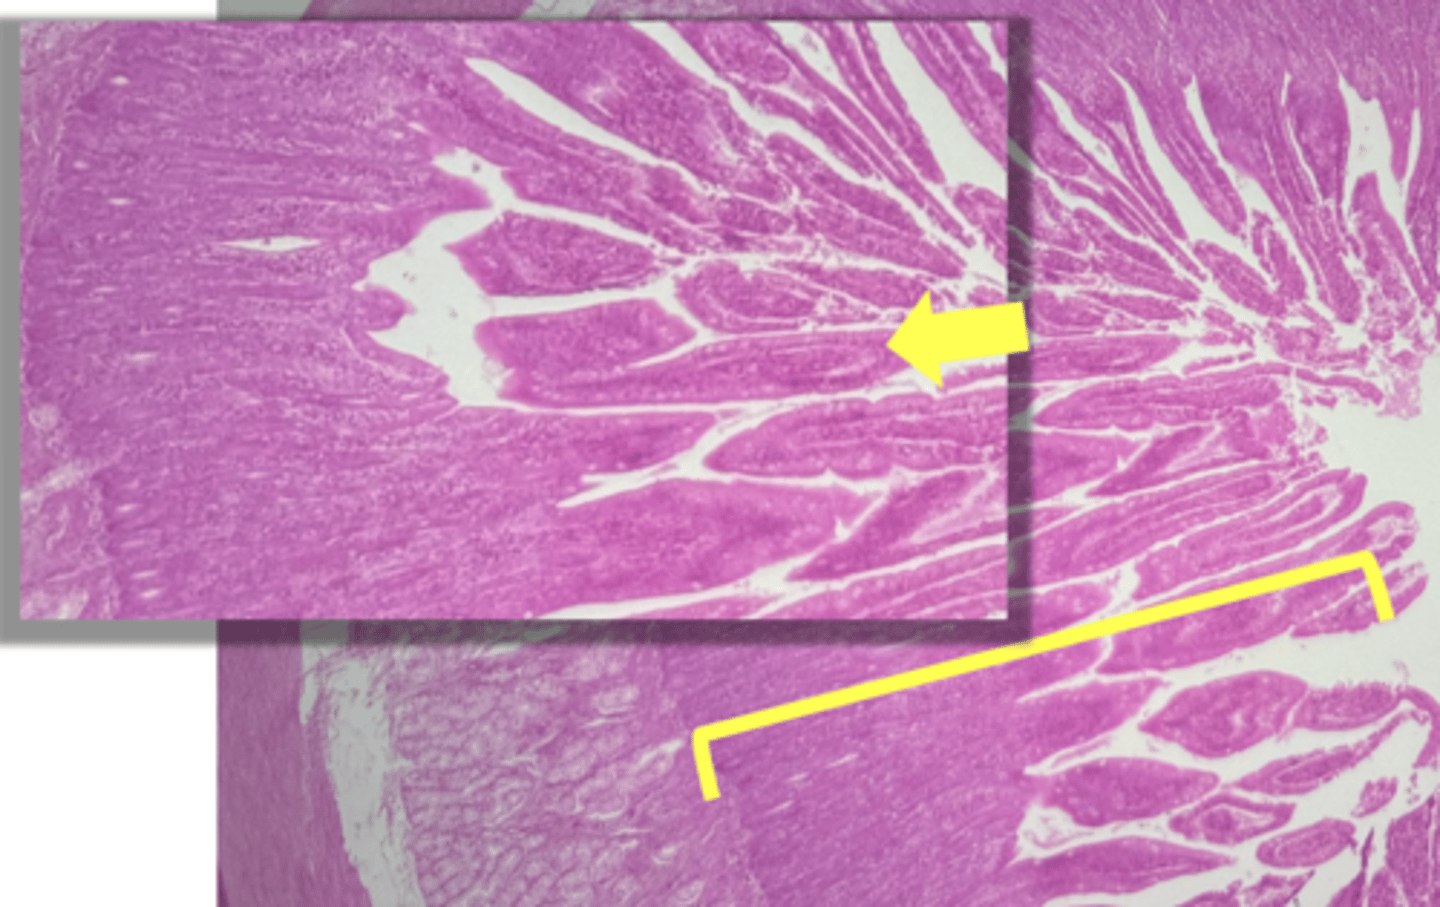

Duodenum (small intestine-cross section)

name the tissue

mucosa

(duodenum)

myscularis externa

Submucosa

Brunner's glands (KEY CHARACTERISTIC)

circular layer

longitudinal layer

Villi (KEY CHARACTERISTIC)

simple columnar epithelium

type of cell

intestinal crypts

lamina propria

muscularis mucosa